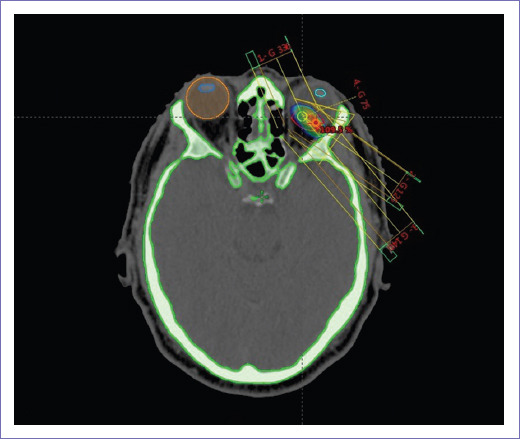

Hombre de 40 años sin antecedentes de importancia, con cuadro clínico de seis meses de evolución caracterizado por escotomas en ojo izquierdo, y disminución de agudeza visual de manera progresiva. Acude a facultativo, quien inicia protocolo de estudio con tomografía de cráneo que reporta imagen hiperdensa con importante reforzamiento en globo ocular izquierdo hacia la cámara posterior, en relación con neoformación de etiología a determinar. Tomografía de tórax y abdomen sin evidencia de enfermedad metastásica. Se refiere al servicio de oftalmología de esta institución, en donde se realiza ultrasonido (USG) modo A-B de ojo izquierdo que reporta tumoración intraocular con dimensiones vertical 8.49 mm, horizontal 9.02 mm, grosor 3.37 mm e imagen sugerente de desprendimiento de retina seroso inferior secundario a tumoración intraocular. Fondo de ojo izquierdo: papila fisiológica, mácula sin alteraciones, lesión hipopigmentada con pigmento naranja, de bordes elevados y bien definidos sobre el territorio de la arcada temporal inferior. Agudeza visual ojo izquierdo 20/50, ojo derecho 20/20, reflejos pupilares normales. Se diagnosticó melanoma coroideo de ojo izquierdo. Se envió al servicio de radioterapia para tratamiento radical con radioterapia externa de intensidad modulada (IMRT), energía de 6 milivoltios (mV), dosis total de 50 Gy en 25 fracciones. Inició el 13 marzo y finalizó el 24 de abril de 2019. Al finalizar tratamiento el paciente mejoró la agudeza visual; al año y medio se mantiene asintomático, agudeza visual conservada y sin datos de actividad tumoral local ni a distancia por estudios de imagen. Las figuras 1 y 2 muestran corte transversal y vista 3D de la planeación del tratamiento en donde se observan las curvas de dosis y distribución de campos de radiación.